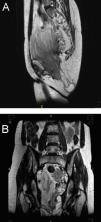

Figuras (3)